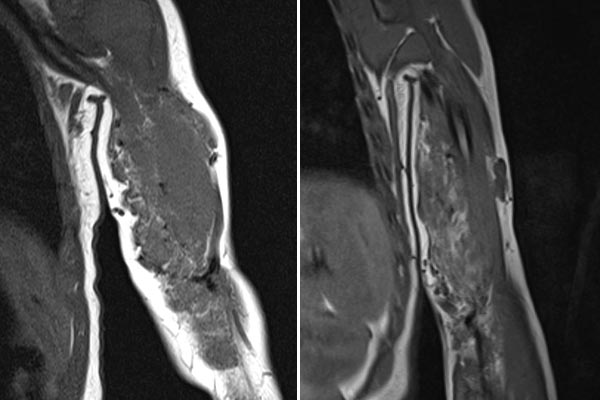

Vergleich der koronaren, T1-gewichteten MRT vom Februar 2019 (linkes Bild) zu September 2021 (rechtes Bild). In dieser T1-Wichtung wird Fett hyperintens (weiß) dargestellt. Im rechten Bild ist gut zu sehen, dass die Fettanteile im Tumor im Laufe der Zeit zugenommen haben. Dies ist typisch für ein teilweise in Involution befindliches infantiles Hämangiom (mehr Fettanteile, weniger Gefäßproliferate).

Zur weiteren Sicherung der Differentialdiagnose wird bei dem Kind auch eine MRT durchgeführt. Hier abgebildet eine koronare, T2-gewichtete, fettunterdrückte STIR-Sequenz. Der Tumor ist hier stark hyperintens (weiß im Bild) und scharf zum umgebenden Gewebe abgegrenzt. Er durchdringt alle Gewebeebenen und enthält zentral als Zeichen einer starken arteriellen Perfusion signalfreie Areale, sogenannte Flow-voids.

Zur weiteren Klärung der Differentialdiagnose wurde nochmals eine MRT durchgeführt, hier wieder abgebildet eine koronare, T2-gewichtete, fettunterdrückte STIR-Sequenz. Der Tumor ist jetzt etwas weniger stark hyperintens (weniger weiß), dies spricht für einen etwas höheren Fettanteil in dieser fettunterdrückten Sequenz. Auch die Perfusion hat etwas abgenommen, es finden sich im Vergleich weniger Flow-voids.